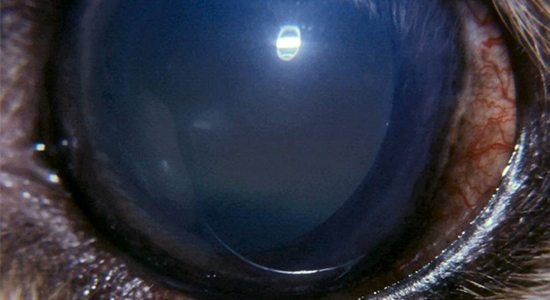

Glaucoma is characterized by progressive damage to the optic nerve of the eye, the most common cause is high eye pressure. If left untreated, glaucoma can lead to blindness. Those with a family history of glaucoma, Diabetes, Systemic hypertension, thyroid disorders and Myopia are at a higher risk of developing it. People above the age of 40 years need to undergo routine eye examinations to rule out glaucoma.

There are several types of glaucoma, and treatment depends on precisely identifying which kind is present. Most forms are progressive and need long-term management. No matter whether the pressure is high, normal, or below normal, it can still cause damage. Some types of glaucoma are chronic and may be present for a lifetime. Other types of glaucoma are acute; that is, they occur suddenly. Currently, glaucoma can be treated and controlled, but cannot be cured completely.